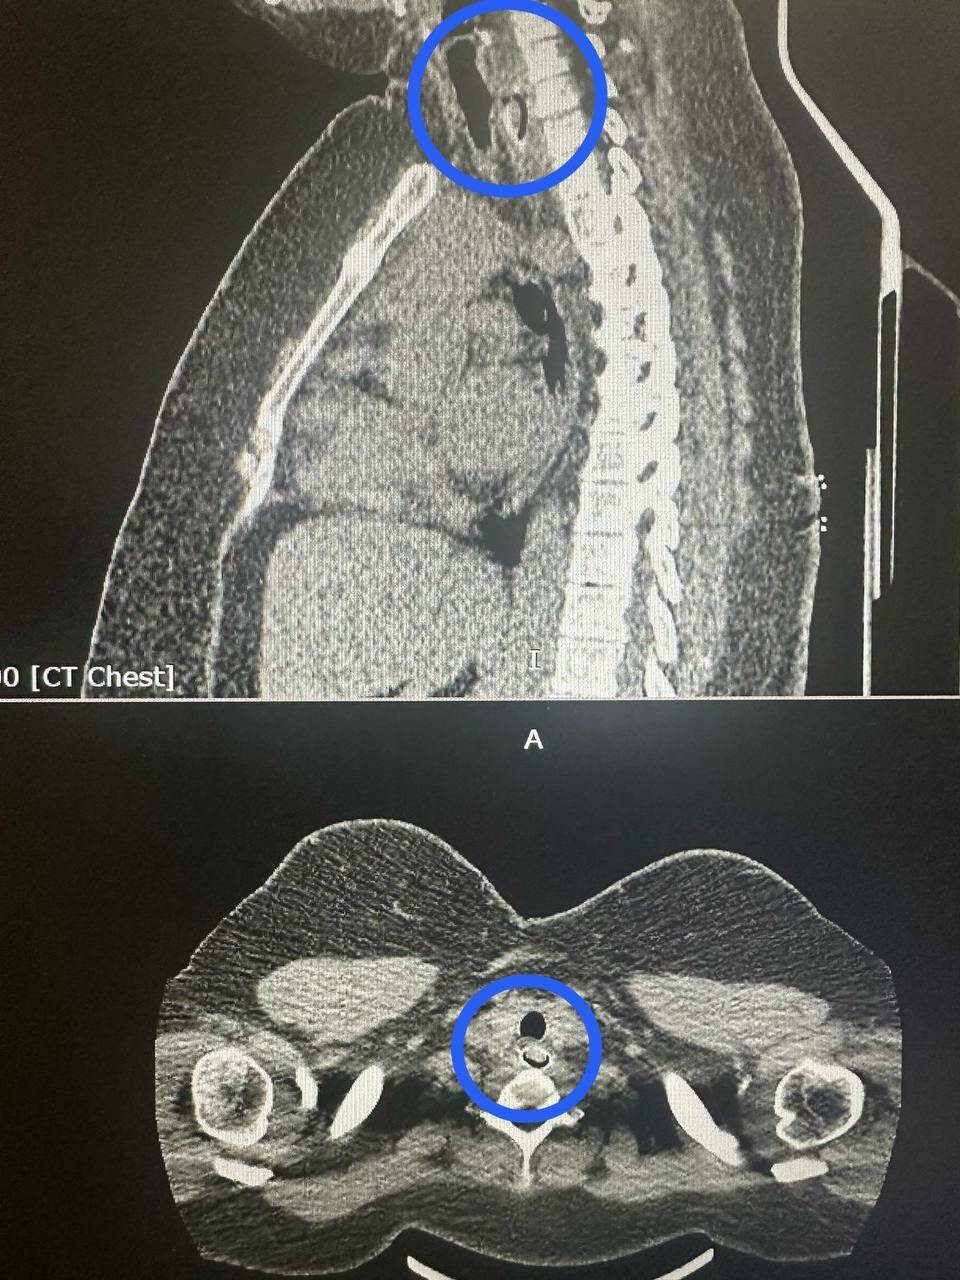

Компьютерная томография показала, что косточка перекрыла почти весь просвет пищевода. Достать ее через рот было невозможно. Поэтому хирурги сделали разрез в области шеи и пищевода, чтобы аккуратно убрать инородное тело.

Фото: РКБ Татарстана